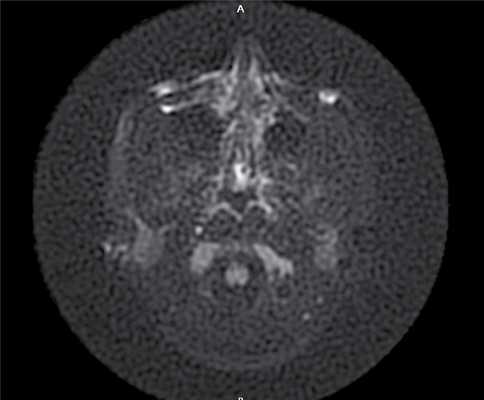

По результатам МРТ головного мозга правая пирамида височной кости деформирована, увеличена в объеме, выполнена субстратом размером до 5,5—2,8—3 см, распространяющимся на область внутреннего слухового прохода, заднего полукружного канала, медиальные отделы барабанной полости, сосцевидный отросток. Описанный субстрат изо-гипоинтенсивен в режиме Т1, гиперинтенсивен — в Т2 и non-EPI DWI (рис. 2). Заключение: признаки рецидива холестеатомы с деструктивными изменениями структур внутреннего и среднего уха на фоне хронических воспалительных изменений.

Рис. 2. Магнитно-резонансная томография головного мозга пациентки М. Деформированная, увеличенная в объеме пирамида височной кости выполнена мягкотканым субстратом.